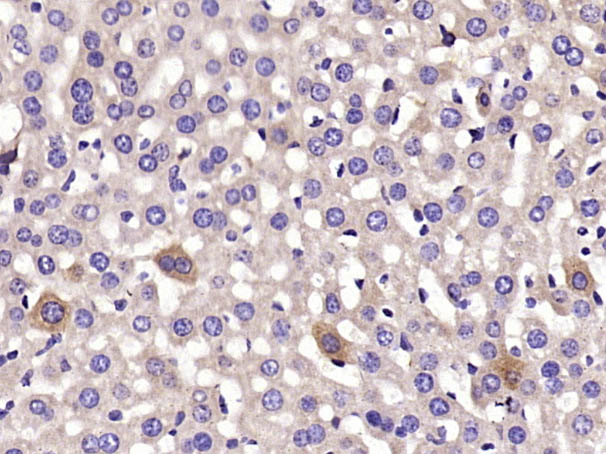

| IHC-P | Mouse | Human, Rat | 1:200-800 |